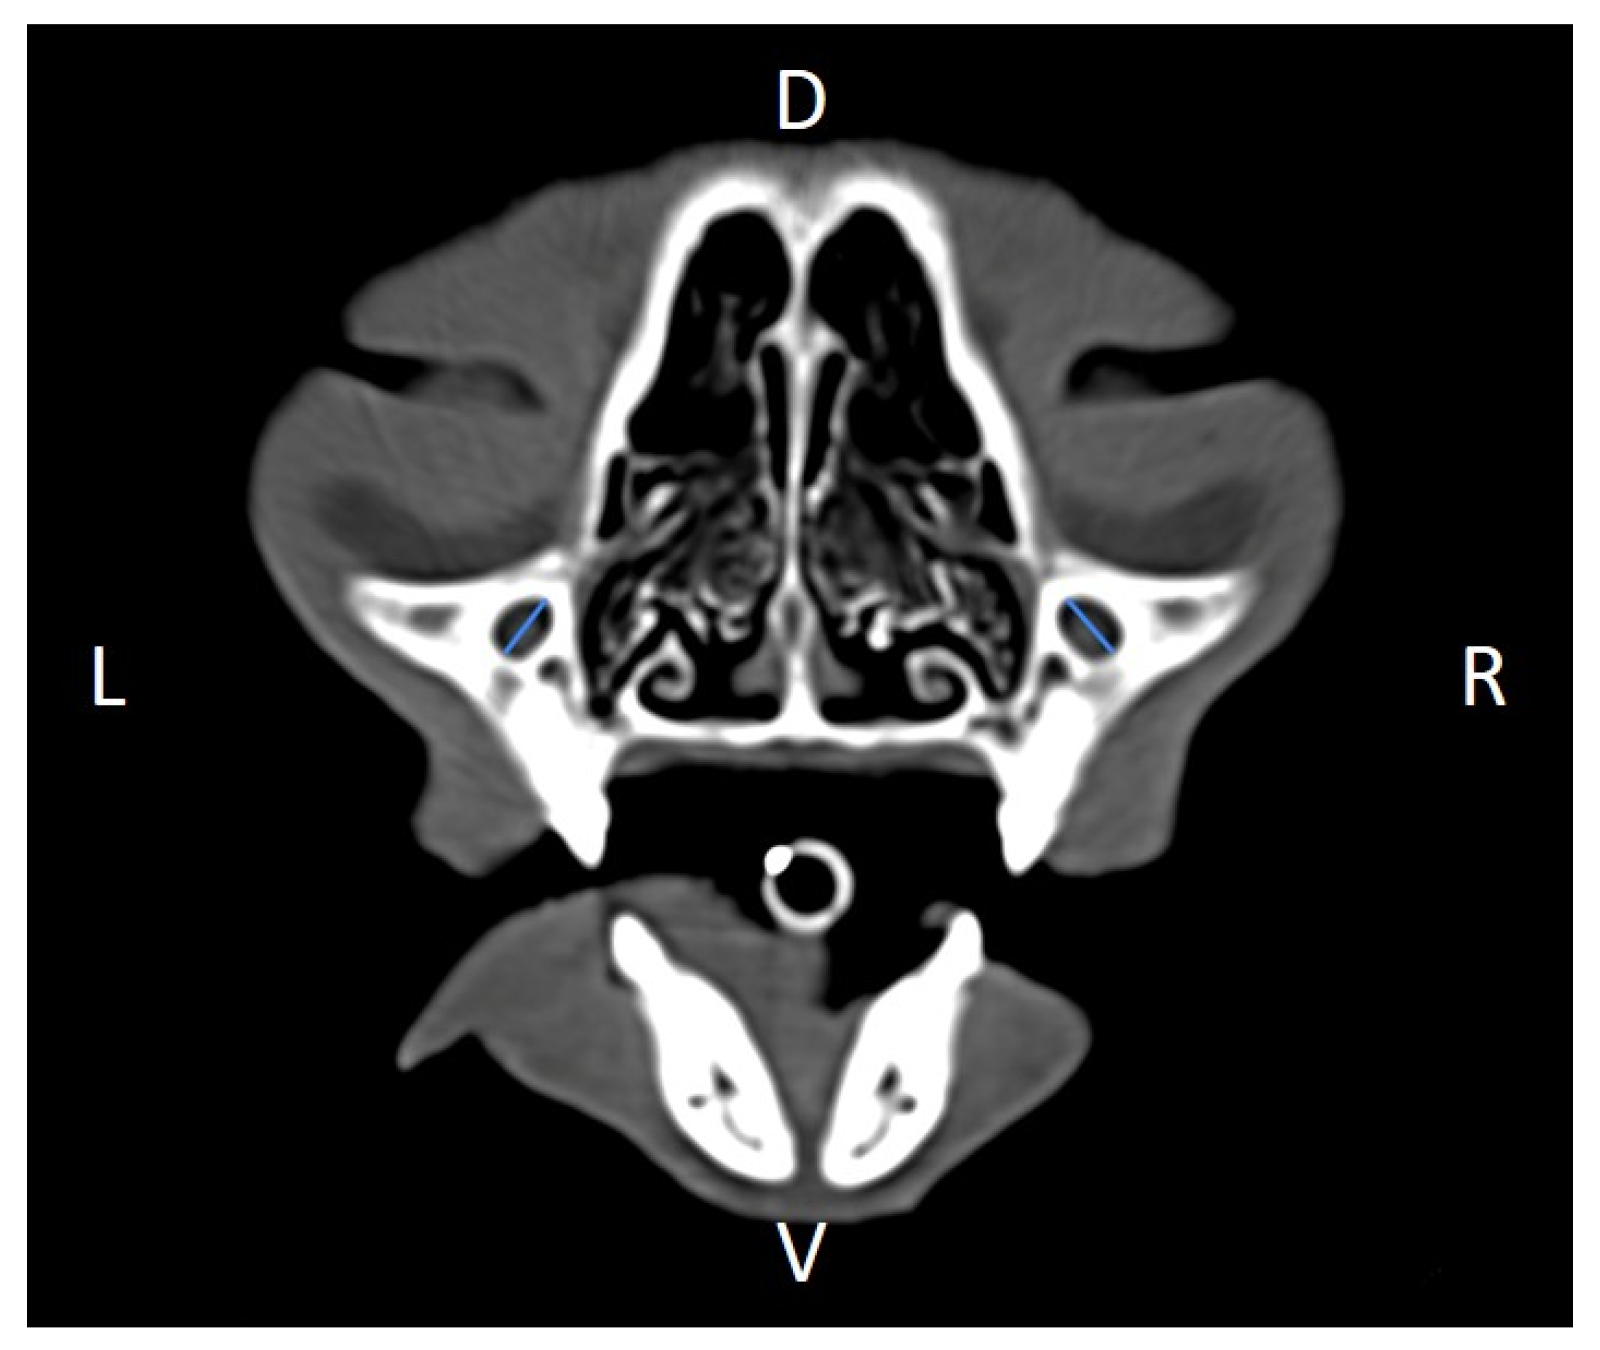

Linear morphometric parameters (Table 1) were obtained directly from CT images using HorosTM v3.3.6.dmg DICOM software with bone filters. Prior to measurement, all images were calibrated from pixels to millimeters. A preliminary study and prior training were conducted, to establish anatomical landmarks that would allow for the repeatability of the measurement methodology by J.F.R., A.R.S., S.A.-P. Recorded variables included infraorbital foramen major axis (Figure 2), minor axis (Figure 3) and length (Figure 4), distance between infraorbital foramina (DIF) (Figure 5), orbital height and width (Figure 6 and Figure 7), zygomatic arch width (Figure 8), skull width and length (Figure 9). Ratios were calculated to normalize for skull size. As preliminary results revealed adequate repeatability of measurements, and in order to reduce the analysis margin of error, two measurements of each studied parameter were performed. The measurements were performed by the same operator (to reduce interpersonal errors), and each measurement of each parameter was performed at different times, in order to reduce intrapersonal errors. Then, the arithmetic mean of the measurements was calculated.

Figure 2. Infraorbital major axis (IFMA) measured at the left and right sides, on a transverse CT image (blue lines). D, dorsal, L, left, R, right, V, ventral.

We found the major axis of the infraorbital foramen to have an oblique orientation relative to the mid-sagittal plane (Figure 2), unlike what has been described in dogs, and, for that reason, naming it total vertical height of the infraorbital foramen seemed inaccurate to us, so we rather named it the infraorbital foramen major axis (IFMA) and the infraorbital foramen minor axis (IFmA) [2].